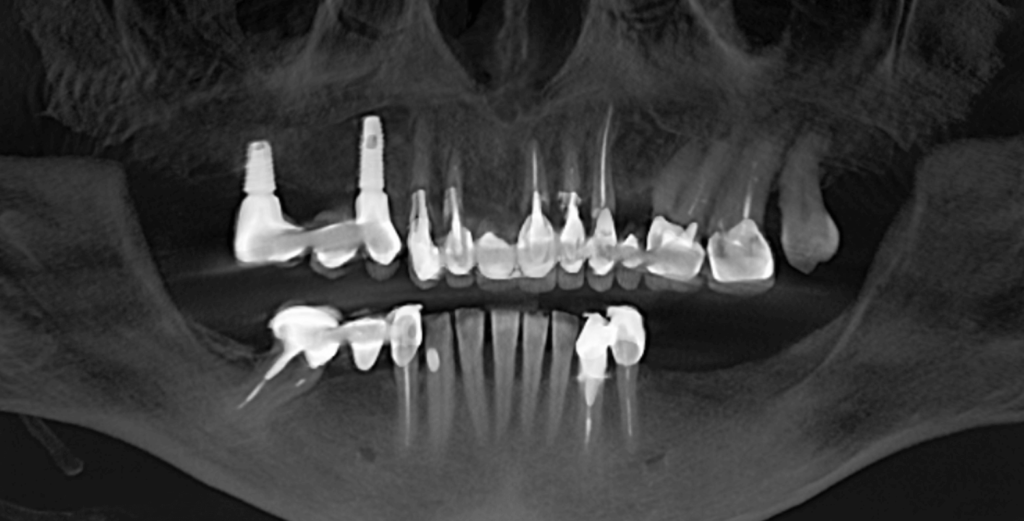

Повторное сканирование и временное протезирование

Подготовленные к протезированию зубы врач отсканировал интраоральным сканером для последующего изготовления постоянных ортопедических конструкций. Сразу после сканирования врач зафиксировал временные зубные протезы, в том числе, для окончательного согласования формы и размера зубов.

8 ЭТАП

Постоянное протезирование конструкциями из диоксида циркония

Несколько дней спустя пациентке сняли временные конструкции и зафиксировали постоянные из диоксида циркония (цвет Bleach 2). Мостовидные протезы в области зубов 14-16, 11-13, 23-27, 35-37, 44-46 и одиночные коронки на зубах 2.1, 2.2, 4.3, 4.2, 4.1, 3.1, 3.2, 3.3, 3.4. Где были старые импланты, зубы 1.4 и 1.6 на них зубной мост закреплен винтовой фиксацией, все остальные конструкции — цементной.

Итог

Наша команда выполнила эту работу за 5 визитов пациентки в клинику в течение 1,5 месяцев. Пациентка счастлива не только благодаря обновленной улыбке, но и благодаря тому, что мы сохранили максимально возможное количество родных зубов.